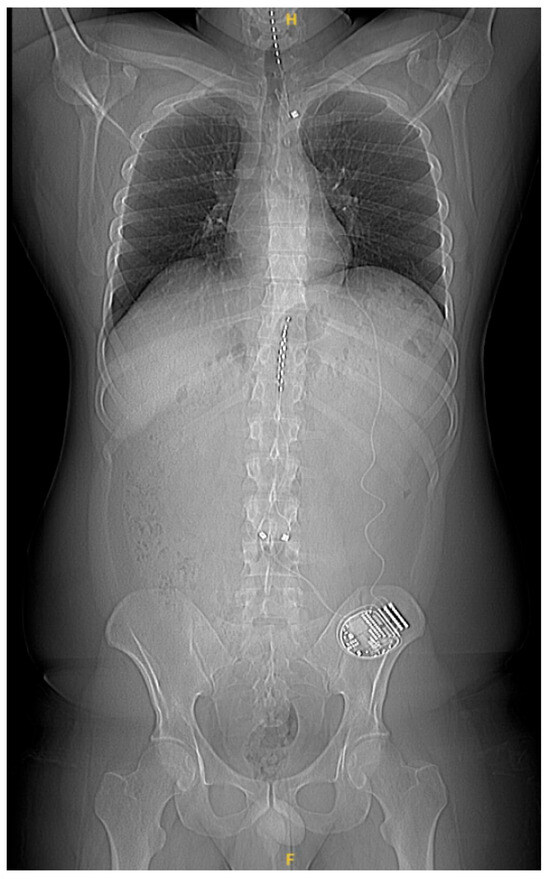

Patients were implanted with epidural percutaneous leads targeting the lower extremities (T10–T11), and upper extremities (C4–C7) if necessary, and with an implantable pulse generator (IPG) system (Alpha WaveWriterTM, Boston Scientific Corporation, Valencia, CA, USA) (Figure 1). The implantation procedure and criteria for permanent implants were based on established standards and were performed in accordance with the center’s standard practice (pain relief ≥ 50% based on a trial phase).

Figure 1.

Typical lead placement.